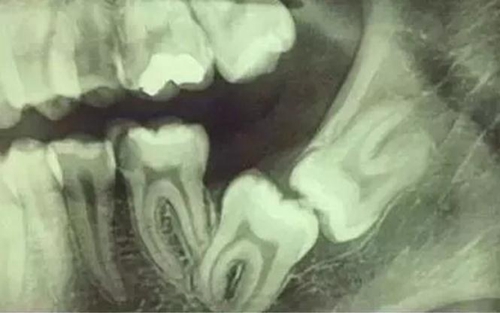

拍片是為了了解智齒周圍情況,也是為了了解智齒結(jié)構(gòu),牙根結(jié)構(gòu)千變?nèi)f化,有可能是融合成一個(gè)根,也可能是八爪根。不同牙根不同位置及方向,只有通過拍片來確認(rèn)。

通過拍片可以了解牙齒本身:生長方向,牙根數(shù)目,牙根是否彎曲,膨大等。

與重要解剖結(jié)構(gòu)的位置關(guān)系:如上頜磨牙與上頜竇的關(guān)系;下頜磨牙與下頜神經(jīng)管的關(guān)系;兒童在混合牙列期恒牙與乳牙胚的關(guān)系等??梢詼p少拔牙的風(fēng)險(xiǎn)。

根神經(jīng)線位置千變?nèi)f化,有些離智齒牙根很遠(yuǎn),有些很近,有些甚至穿過智齒根部。